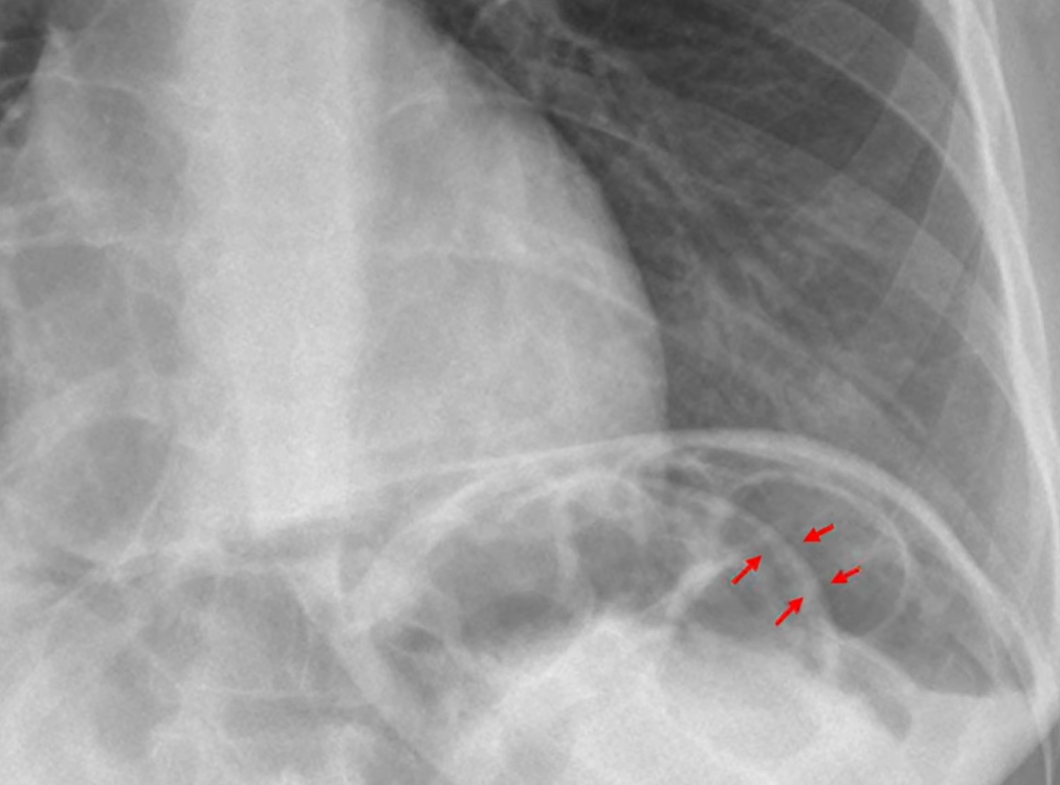

The red arrows indicate the upper border of the (BLANK).

B) Liver